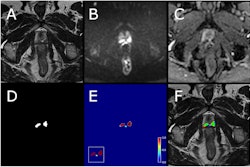

Assessment of the use of MRI to evaluate this kind of skeletal muscle change complexity is limited, so the researchers investigated the effects of a 12-week intervention on 187 obese individuals (average body mass index, 34.8 kg/m²) that combined time-restricted eating and supervised exercise on changes in mid-thigh skeletal muscle tissue using 3-tesla MRI, comparing this protocol to time-restricted eating plus supervised exercise, each of these alone, and "usual care" (defined as open eating and exercise schedules).

The intervention consisted of a Mediterranean diet-based education program; self-selection of an eight-hour eating window for the time-restricted eating and time-restricted eating plus exercise groups; and for the exercise and time-restricted eating plus exercise groups, 24 supervised sessions that combined resistance and high-intensity interval aerobic training, plus a weekly walking program. The team used MRI to quantify mid-thigh skeletal muscle tissue area at baseline and after the intervention.